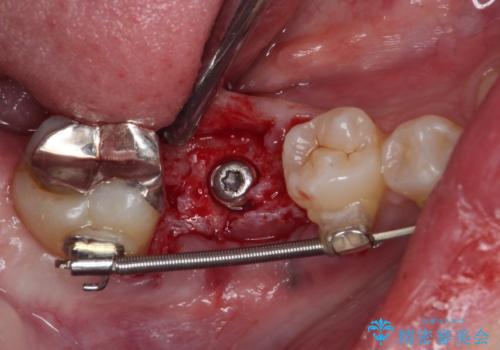

また、右下の抜歯が必要な奥歯は、矯正治療の途中でインプラントを埋入し、矯正治療後に上顎と合わせて補綴治療を行うこととしました。

- 外科手術のため、術後に痛みや腫れ、違和感を伴います

- メンテナンスを怠ったり喫煙により、お口の中に大きな悪影響を及ぼすインプラント周囲炎等にかかる可能性があります